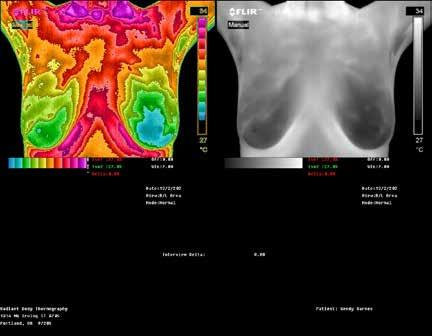

RADIANT BODY

THERMOGRAPHY

The Canary in the Coal Mine

RADIANT BODY THERMOGRAPHY

Candace Parmer

Clinical Thermographic Technician 503-775-1812

RadiantBodyThermography.com

CBD Oil

Call to learn how we can assist you and your doctor in protecting breasts from disease, excess hormonal activity and over diagnos breast cancer. See ad, page 17.